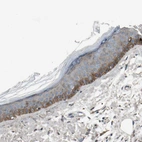

Immunohistochemical staining of human cerebral cortex, gastrointestinal, lymph node and skin using Anti-MST1R antibody HPA008180 (A) shows similar protein distribution across tissues to independent antibody HPA007657 (B).